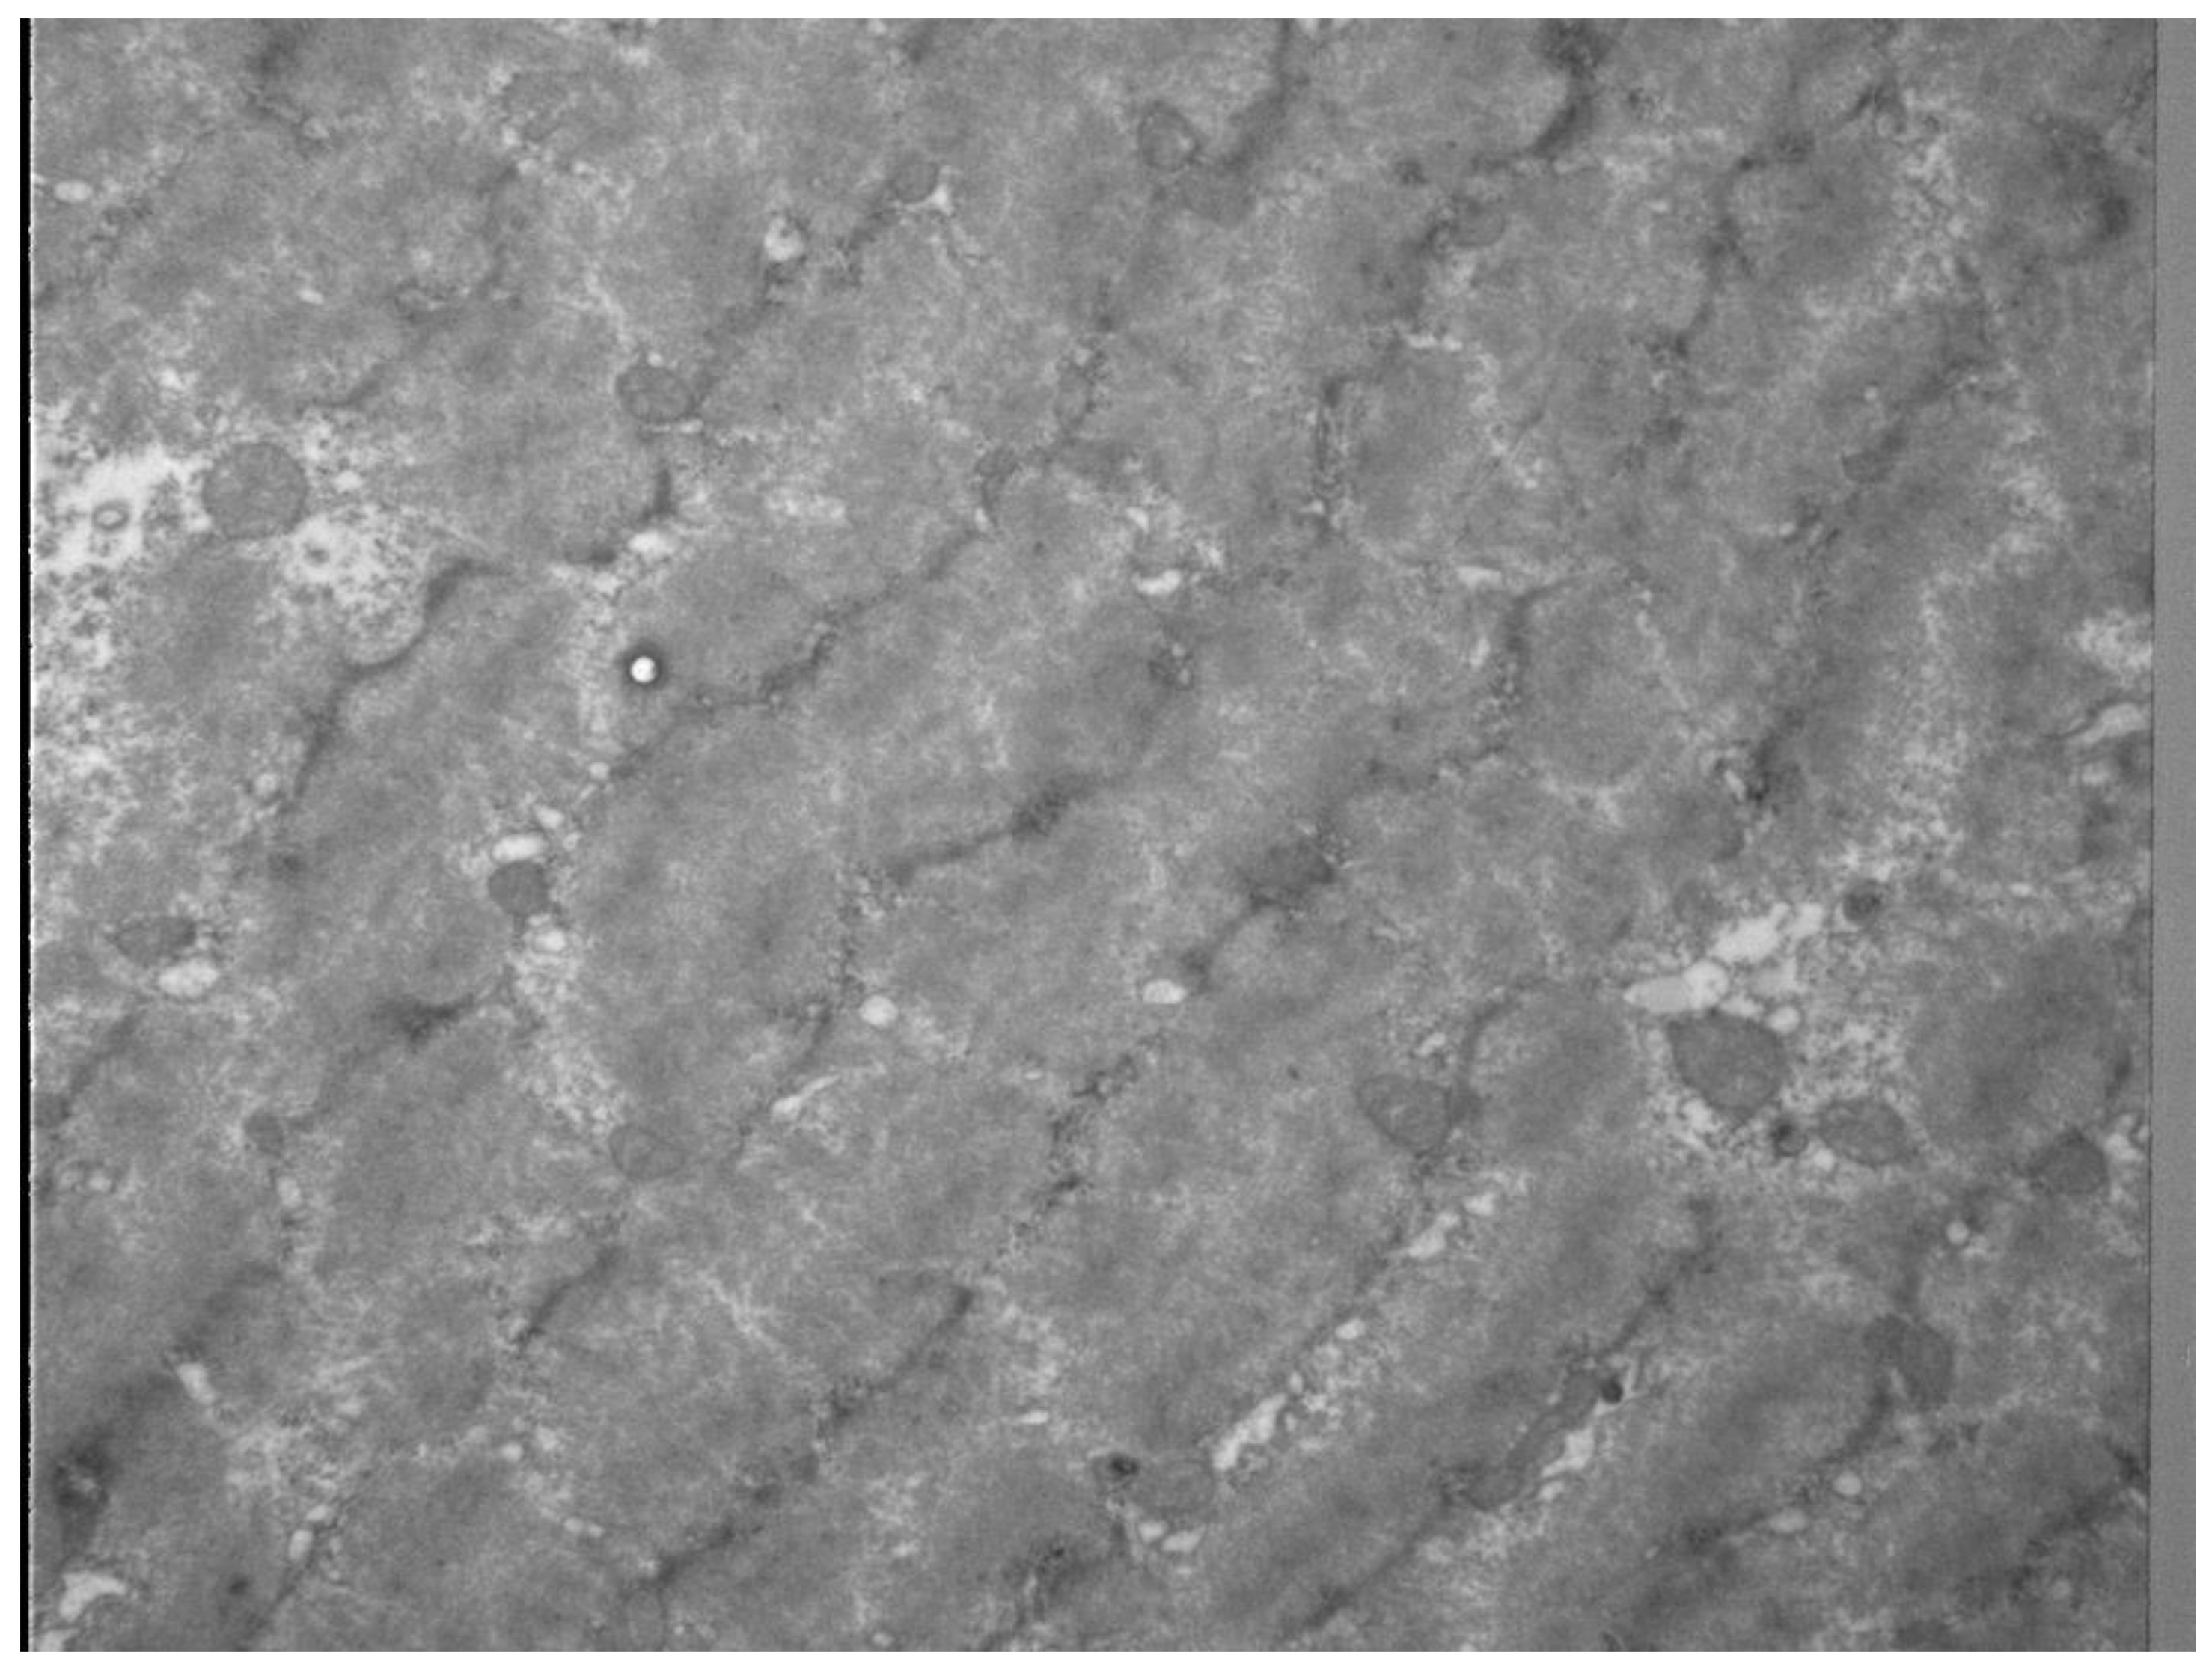

- Hotfiel, T.; Freiwald, J.; Hoppe, M.W.; Lutter, C.; Forst, R.; Grim, C.; Bloch, W.; Huttel, M.; Heiss, R. Advances in Delayed-Onset Muscle Soreness (DOMS): Part I: Pathogenesis and Diagnostics. Sportverletz. Sportschaden 2018, 32, 243–250. [Google Scholar] [CrossRef] [PubMed]

- Hotfiel, T.; Kellermann, M.; Swoboda, B.; Wildner, D.; Golditz, T.; Grim, C.; Raithel, M.; Uder, M.; Heiss, R. Application of Acoustic Radiation Force Impulse (ARFI) Elastography in Imaging of Delayed Onset Muscle Soreness (DOMS): A Comparative Analysis With 3T MRI. J. Sport Rehabil. 2017, 1–29. [Google Scholar] [CrossRef]

- Kellermann, M.H.M.; Swoboda, B.; Gelse, K.; Freiwald, J.; Grim, C.; Nagel, A.; Uder, M.; Wildner, D.; Hotfiel, T. Intramuscular perfusion response in delayed onset muscle soreness (DOMS): A quantitative analysis with contrast-enhanced ultrasound (CEUS). Int. J. Sports Med. 2017, 38, 833–841. [Google Scholar] [CrossRef] [PubMed]